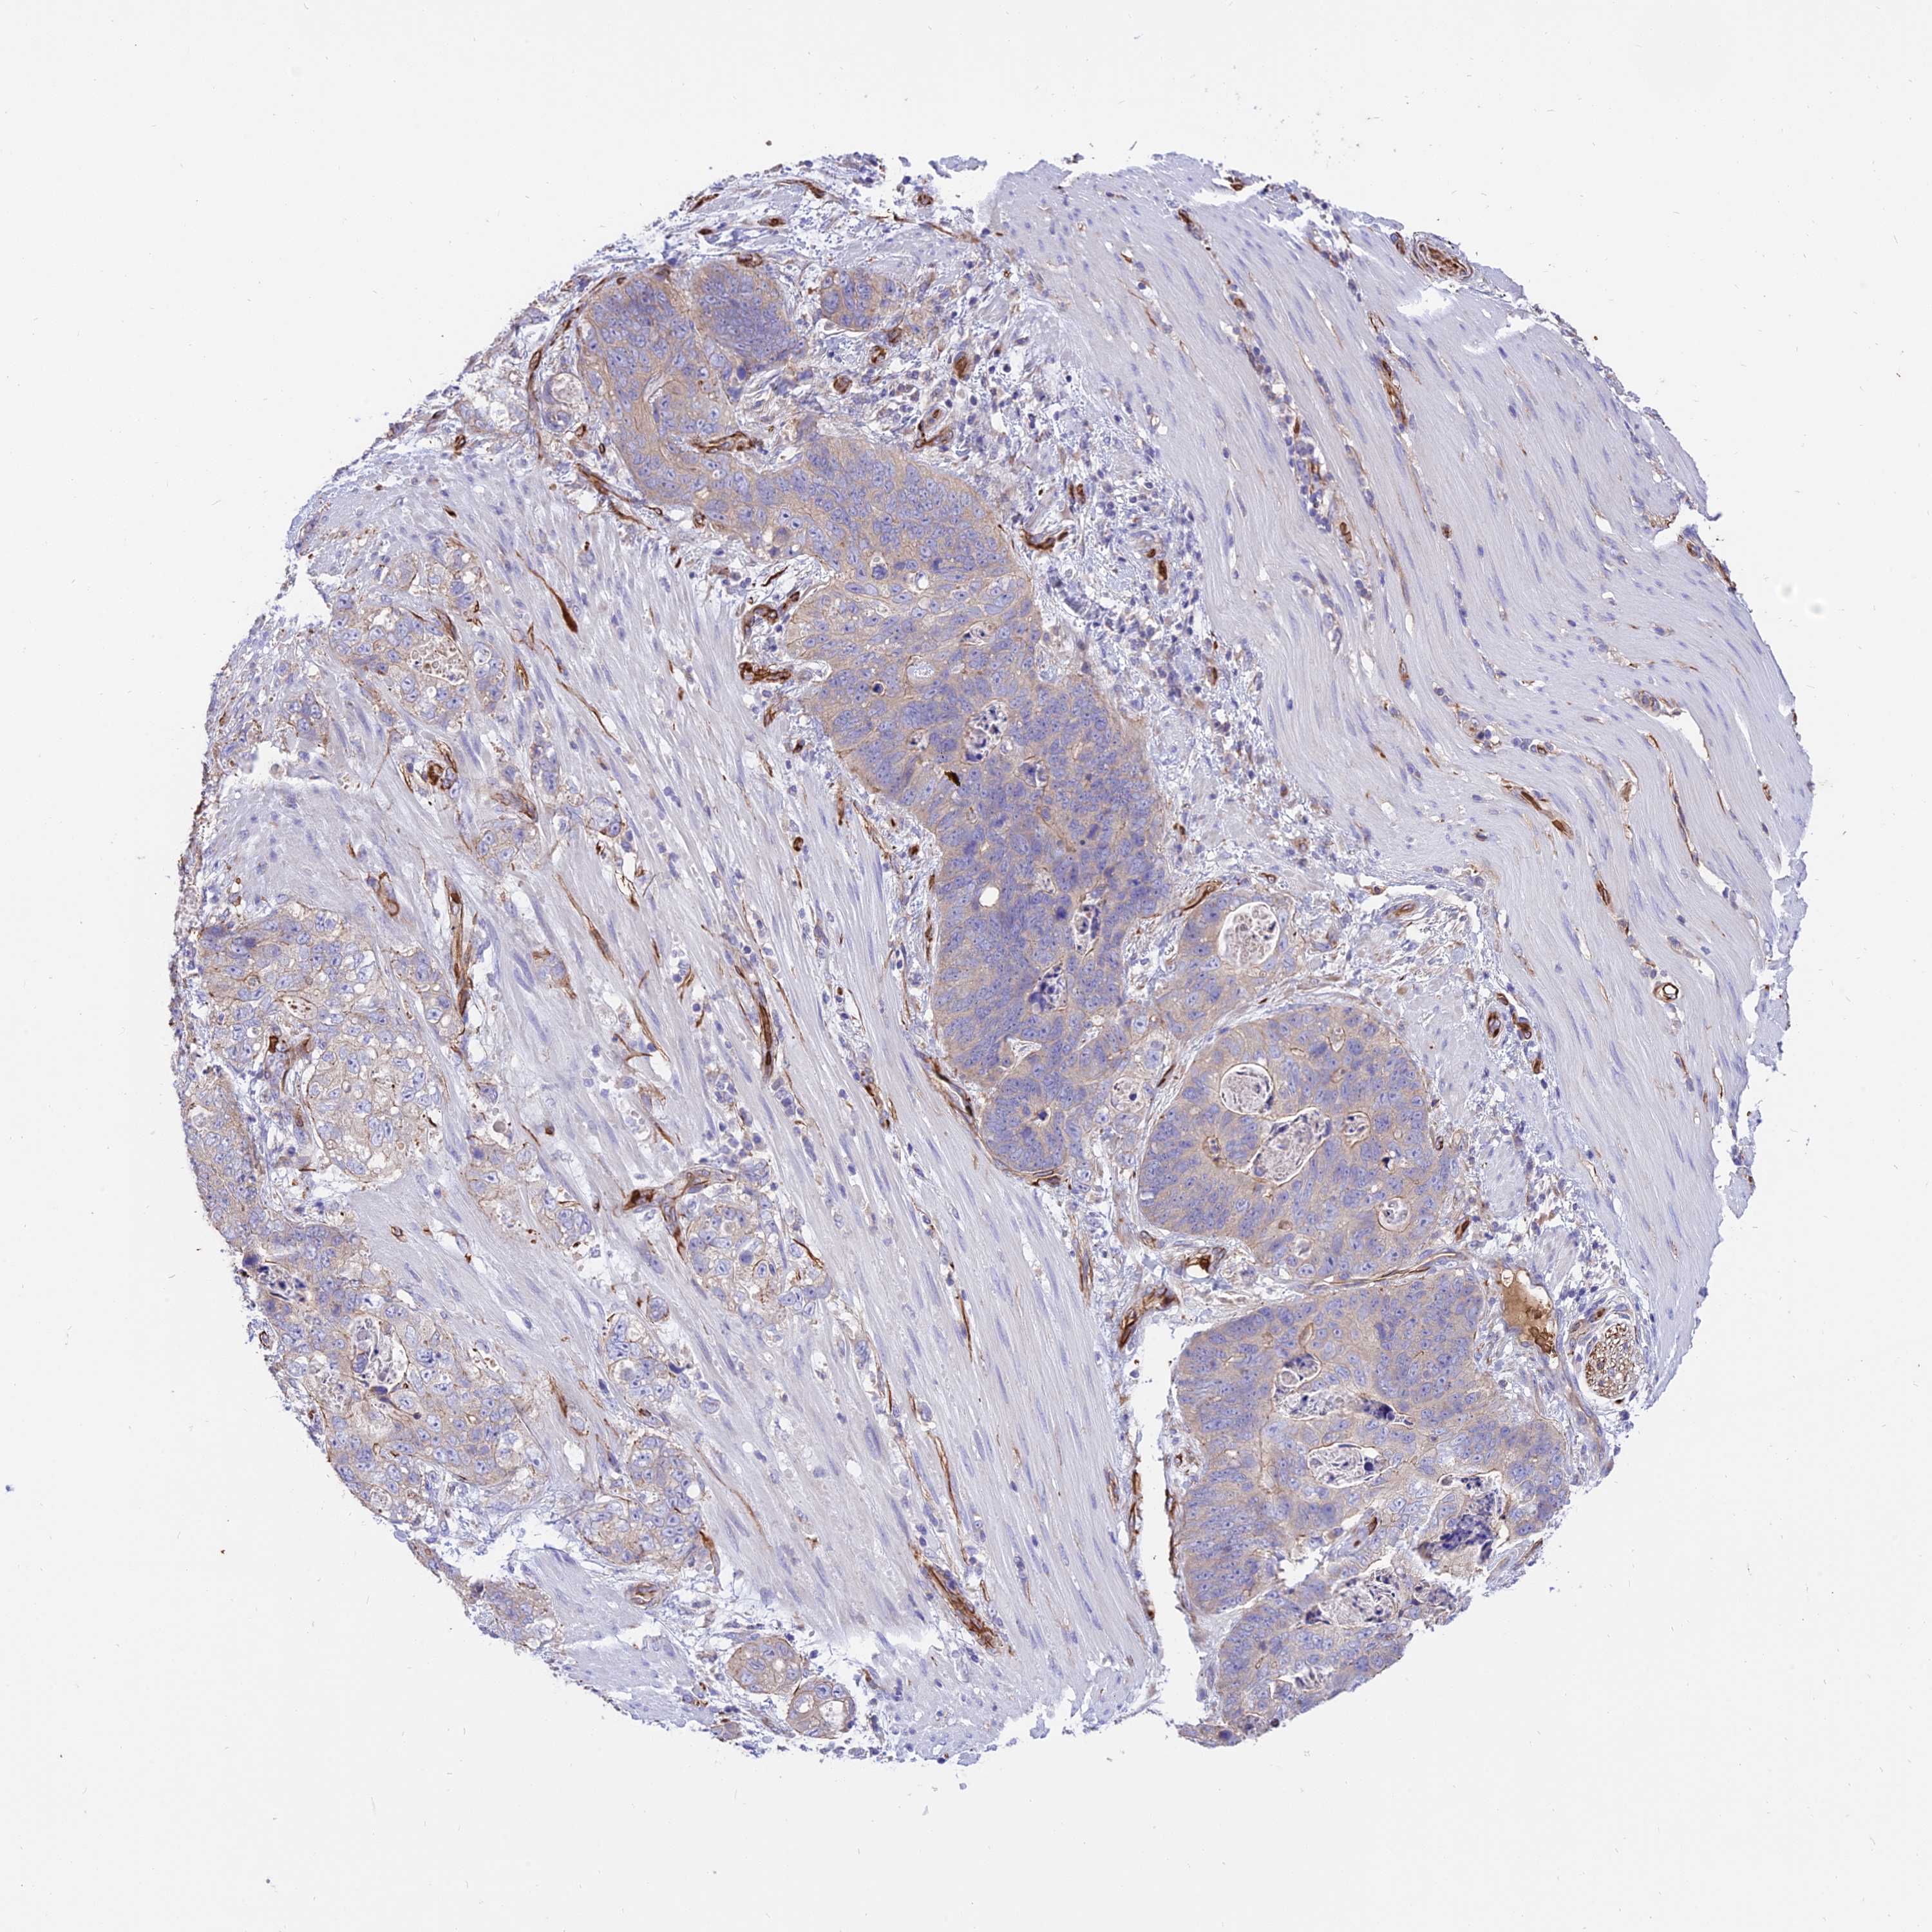

STOMACH CANCER - Protein expressioni

A mouse-over function shows sample information and annotation data. Click on an image to view it in a full screen mode. Samples can be filtered based on level of antibody staining by selecting one or several of the following categories: high, medium, low and not detected. The assay and annotation is described here.

Note that samples used for immunohistochemistry by the Human Protein Atlas do not correspond to samples in the TCGA dataset.

Antibody stainingi

Antibody staining in the annotated cell types in the current human tissue is reported as not detected, low, medium, or high, based on conventional immunohistochemistry profiling in selected tissues. This score is based on the combination of the staining intensity and fraction of stained cells.

Each image is clickable and will lead to virtual microscopy that enables deeper exploration of all samples and also displays staining intensity scores, fraction scores and subcellular localization as well as patient and tissue information for each sample.

Antibody HPA041608

Antibody HPA042459

Staining

High

Medium

Low

Not detected

Intensity

Strong

Moderate

Weak

Negative

Quantity

>75%

75%-25%

<25%

None

Location

Nuclear

Cytoplasmic/membranous

Cytoplasmic/membranous,nuclear

Adenocarcinoma, NOS